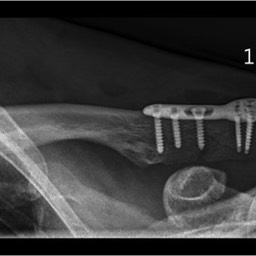

What do clavicle fractures look like on X-ray?

Below are examples of typical fractures that benefit from surgery.

Click an image to enlarge